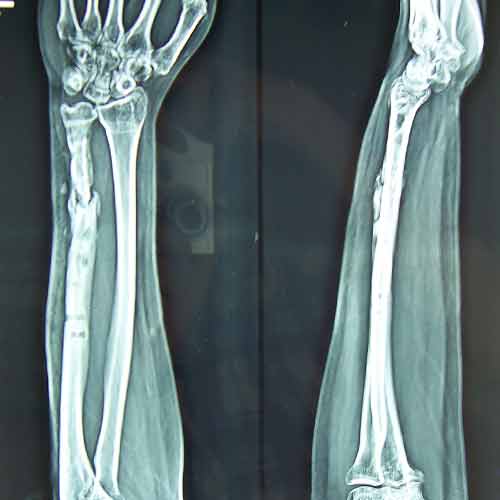

Case:6 Segmental Comminuted Fracture Radius

Patient, aged 75 years during morning walk tripped & had a fall following which he sustained injury to the left forearm. Closed reduction & interval fixation with Intra-medullary TEN nails was done in radius & ulna. Now he has full supination & pronation function of forearm.

Pre-Op

Post-Op